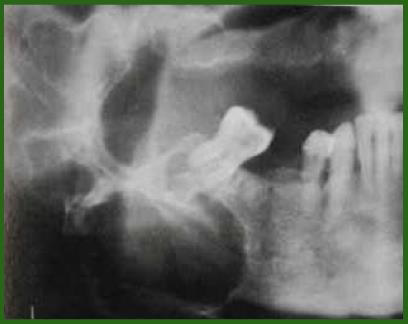

Sialolithiasis (唾液腺結石症) 和鈣、磷的代謝無關 Submandibular gland -

• 單發

• 用餐 30mins 痛

• 硬、不移動

• 檢測需要 occlusal film

alt text